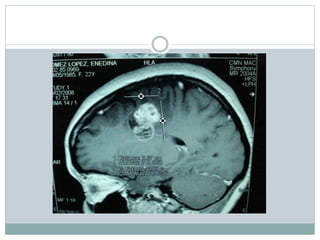

RM tumoracion

RM

Metastasis cerebral por sarcoma en muslo

Metastasis del sarcoma en muslo

Tumor cerebral